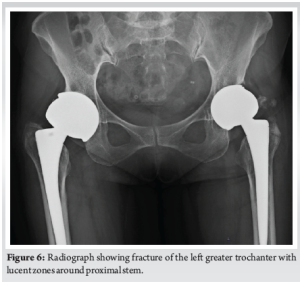

A 63-year-old female who presented to our outpatient department with complaints of bilateral hip pain, more pronounced on the left side, accompanied by a limp for the past 3 months. The patient had undergone bilateral MOM THRs 15 years ago (VerSys Fiber Metal tapered femoral stem with Metasul Component- Metal on Metal articulation, Zimmer Biomet, USA) due to secondary osteoarthritis, and had experienced an uneventful post-operative course until the recent onset of symptoms. On clinical evaluation and radiographic imaging, a fracture of the left greater trochanter was identified, along with lucent zones in both femurs (Fig. 6). Laboratory tests ruled out infection, and MARS MRI revealed features suggestive of metal on metal pseudotumor which confirmed the presence of metallosis. Elevated serum cobalt and chromium levels of 227 mcg/L (normal range 0.01–0.91) and 104 mcg/L (normal range 0.70–28) further supported the diagnosis.